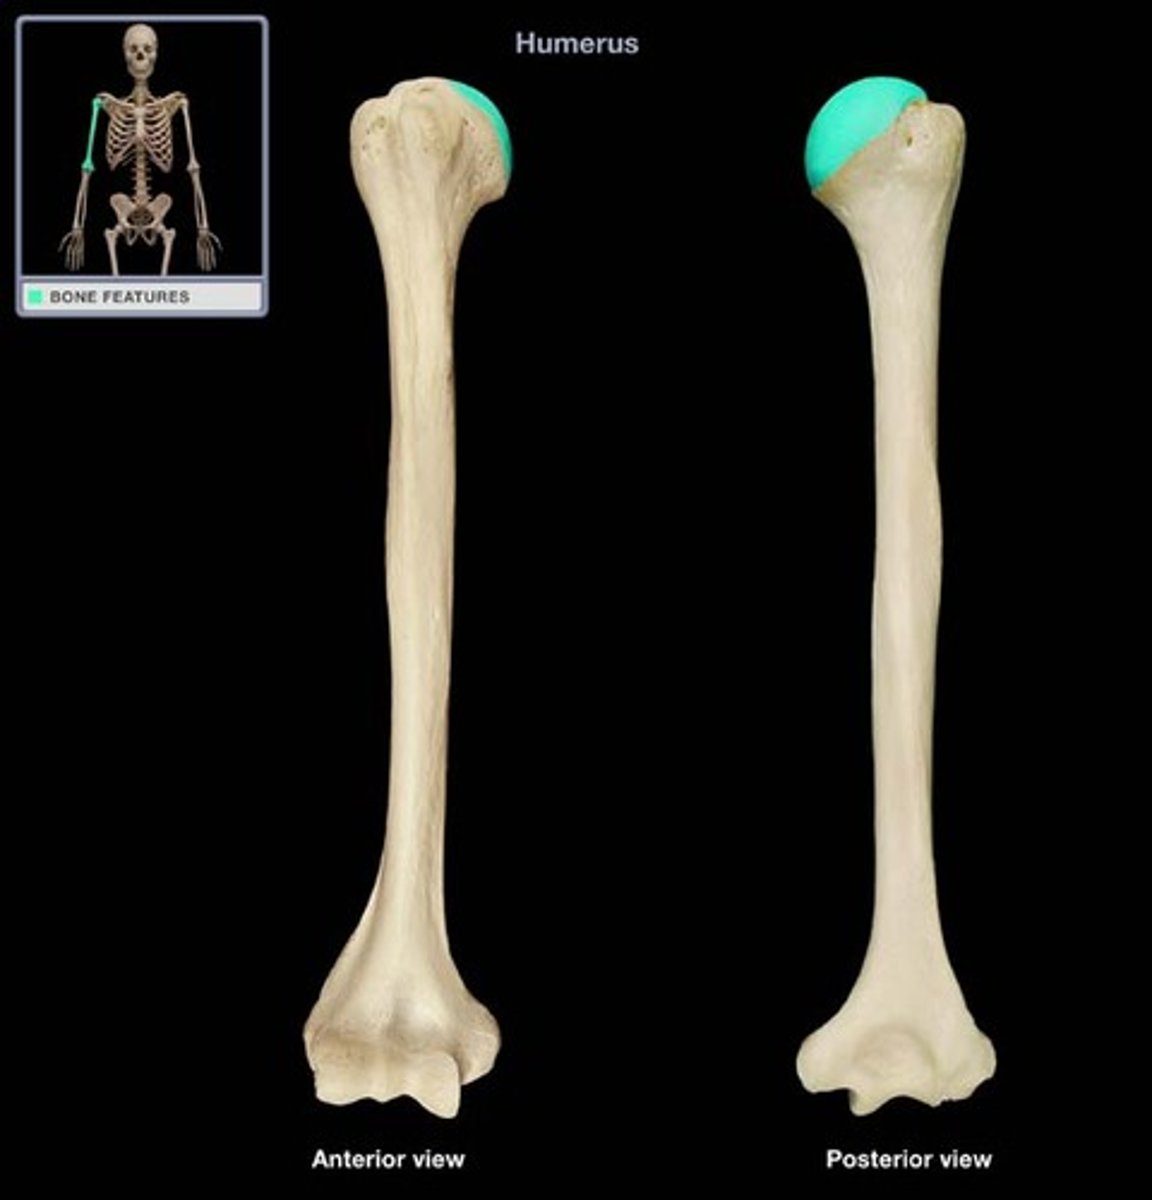

The humerus is the ______ bone in the UE

largest

What bones do the humerus articulate with?

- scapula via glenohumeral joint

- radius & ulna via elbow joint

Features of the humerus:

Head of the humerus:

articulates with glenoid cavity of scapula